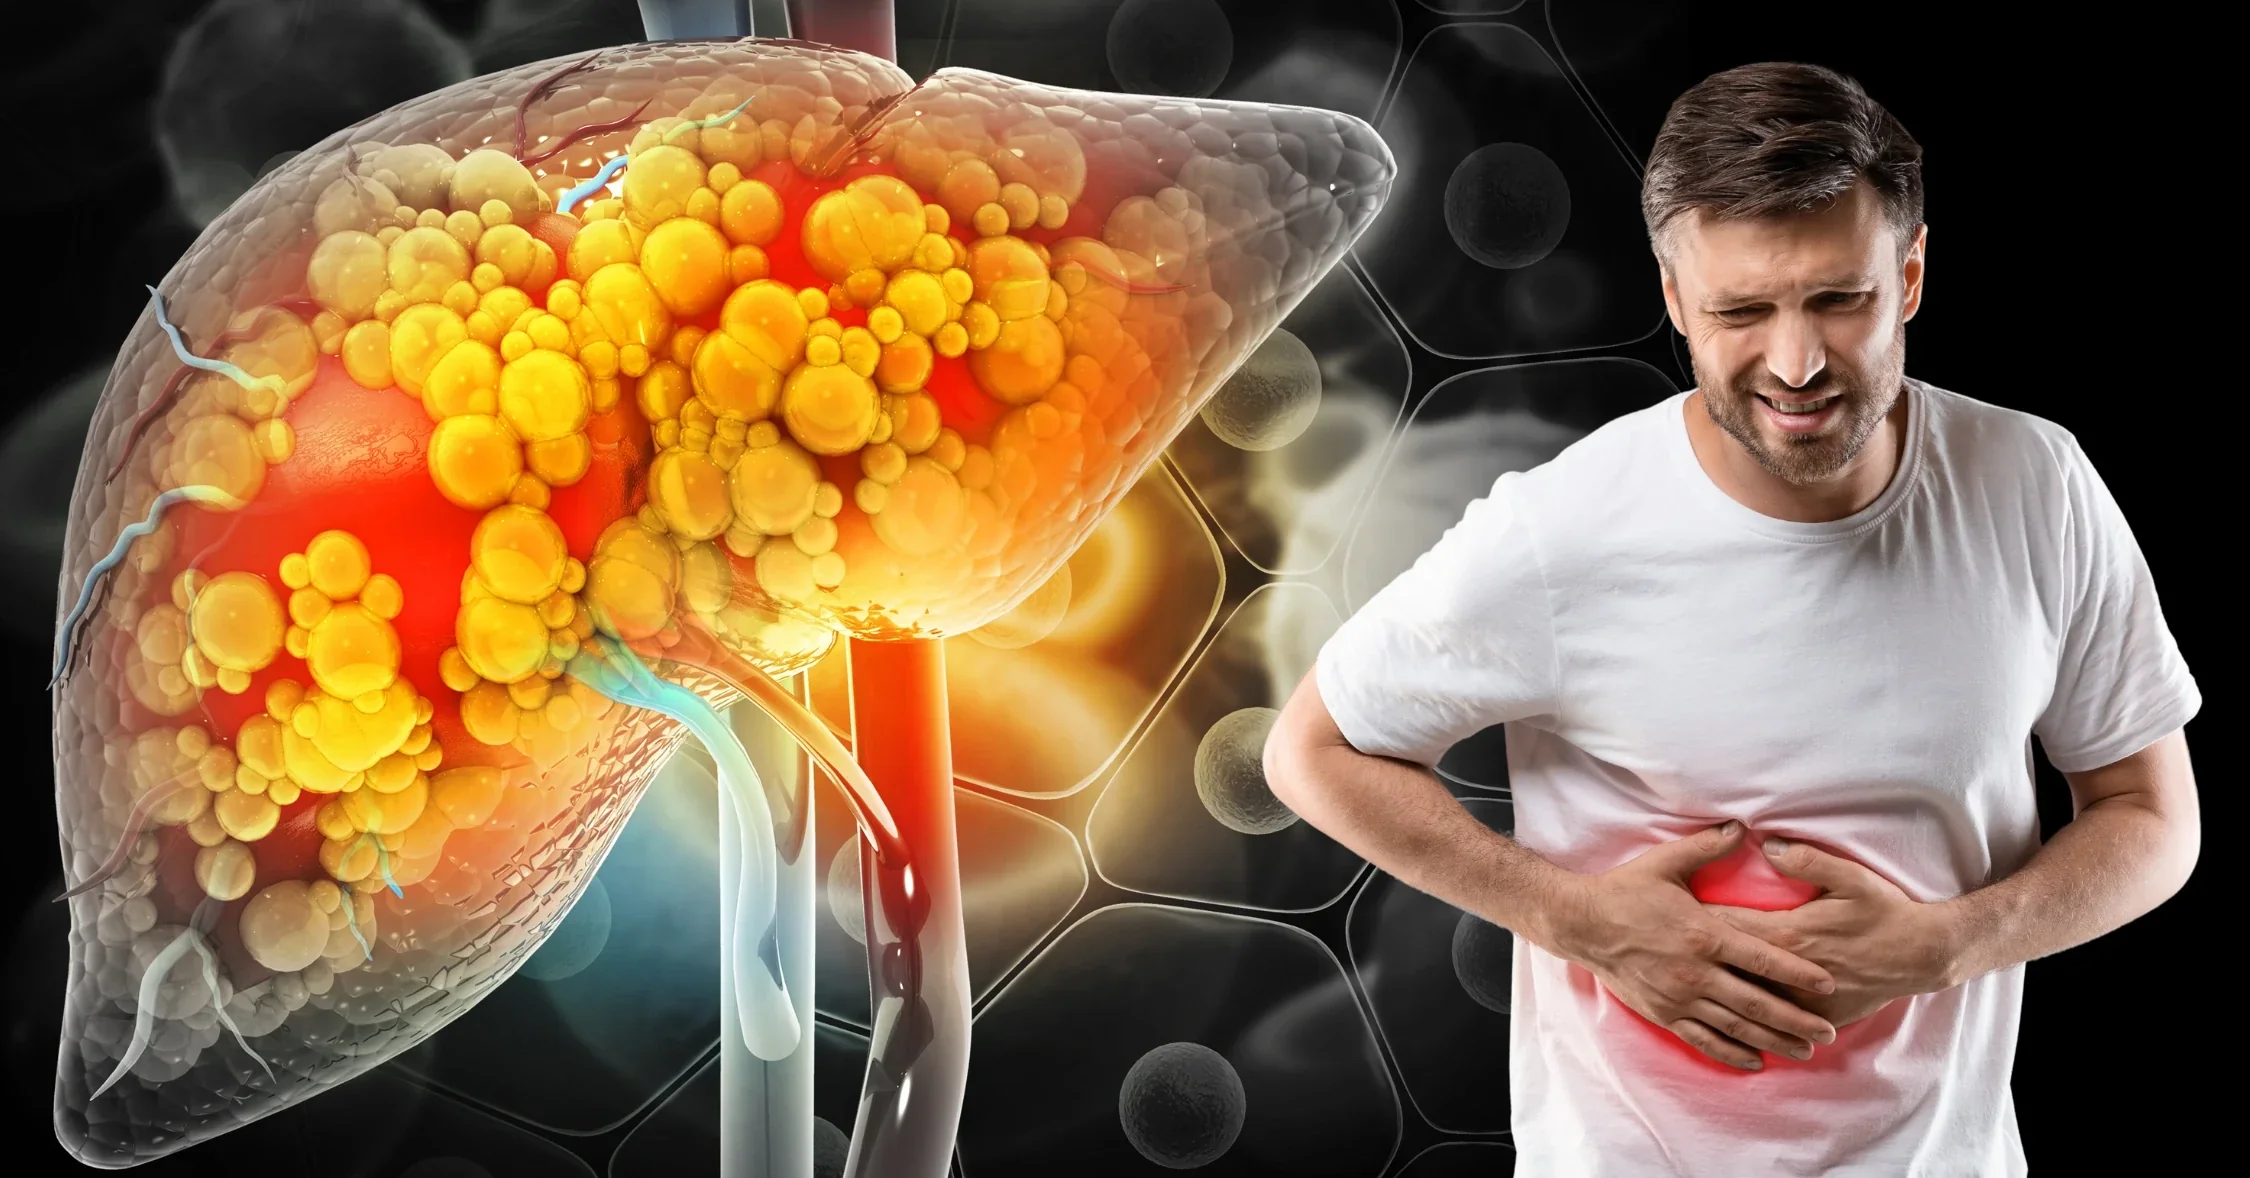

Fatty liver disease is becoming very common today. In simple words, fatty liver happens when extra fat builds up inside the liver. At first, this condition may not cause pain. However, if ignored, it can slowly damage the liver. Therefore, early care is very important.

Fatty liver disease occurs when fat accumulates in liver cells. Normally, a small amount of fat is present in the liver. However, when fat becomes excessive, problems may begin.

- Mild pain in the upper right abdomen

Fatty liver may seem harmless at first. However, untreated fatty liver can lead to inflammation. Over time, this may cause liver damage.